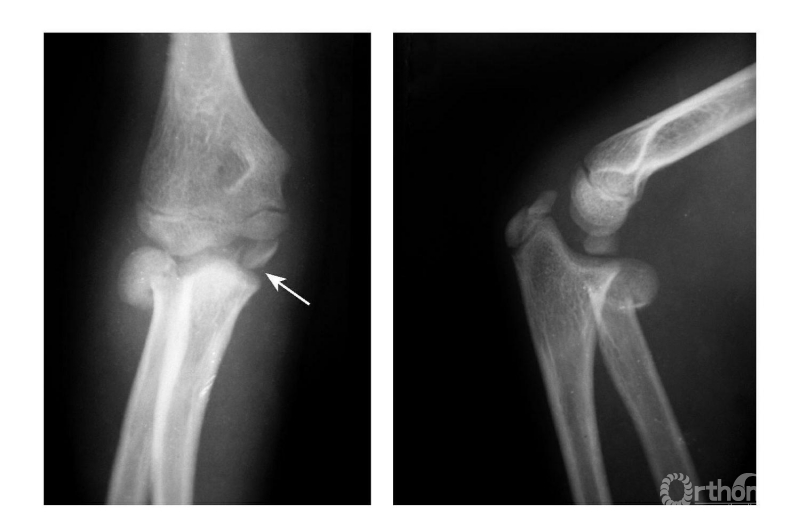

例2:内上髁撕脱骨折,骨块移至尺肱关节间(成人)(图7)。

图7

例3:肱骨内上髁Ⅲ度骨折并桡骨颈骨折(歪戴帽)(图8)。

图8

Ⅳ度损伤:

例1:肘关节外后脱位并肱骨内上髁撕脱骨折,骨块移向尺肱关节间(图9)。

图9